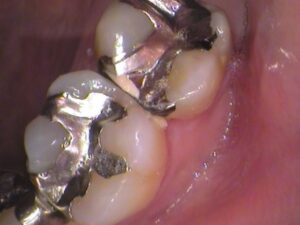

お口の中を見てみると

上の奥歯ですが、銀歯が入っています。

何年も前に虫歯治療をしたときに銀歯になったそうです。

この銀歯の中で虫歯が広がっています。